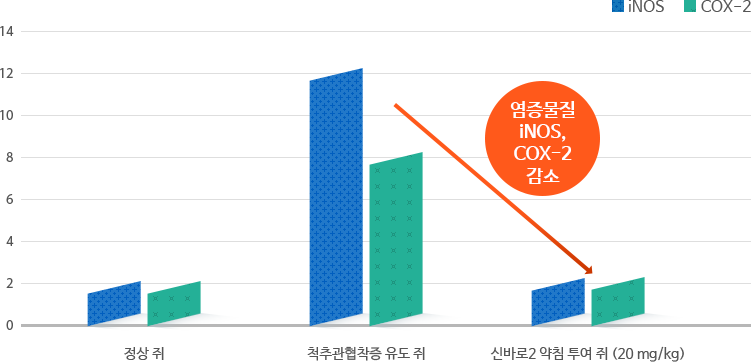

척추관협착증 치료법 신바로2약침, 통증감소 및 척수회복 효과 입증

통증을 유발하는 염증물질 감소

척추관협착증을 유도한 쥐에 자생 신바로2 약침을 투여하자 통증을 유발하는 염증물질(iNOS, COX-2)이 감소했습니다.